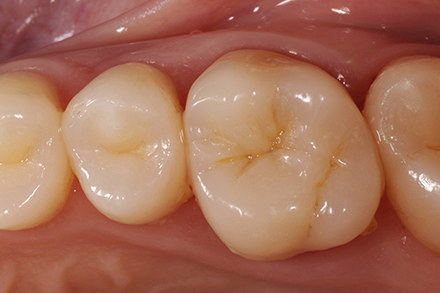

Occlusal anatomy

A different point of view which shows clearly the occlusal anatomy and the translucency effects.